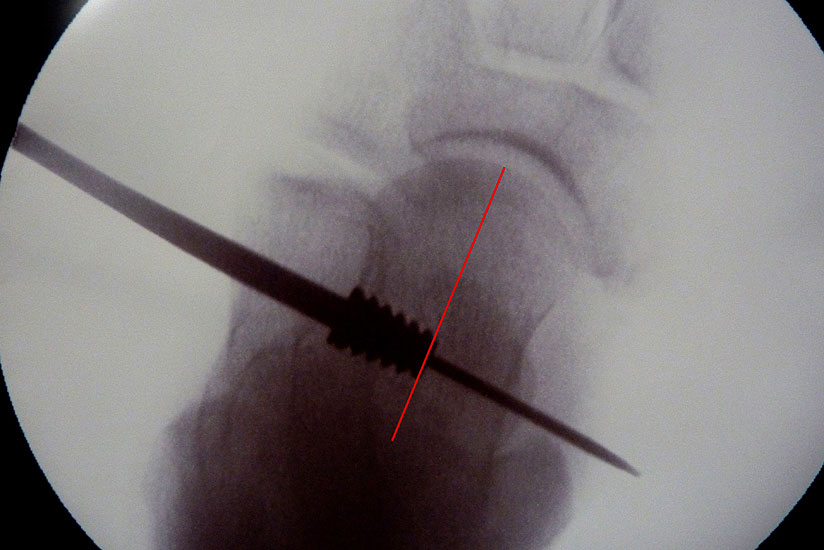

• Sehr sicheres Verfahren sobald der Führungsdraht im Sinus tarsi platziert ist. Das zugehörige Instrumentarium, alle Probeimplatate und auch das endgültige Implantat sind kanüliert und werden stets über diesen Guidepin geführt.

• Fehlplatzierungsrisiko durch Führungsdraht und Durchleuchtungskontrolle gering.

• Primäre Fehlplatzierung (Gefahr durch System mit Führungsdraht gering).